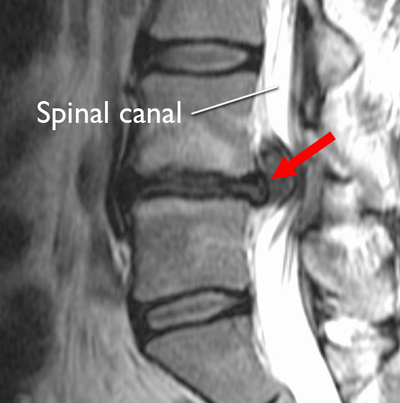

Many are surprised to learn that a chiropractor can reduce acute and chronic pain after the first appointment. The diagnostic images showcased below are a testament to what an experienced chiropractor can do for your spinal injuries and overall health.

TBI | Concussions | Whiplash | Neck Pain | Headaches and Migraines | Back Pain | Shoulder Pain | Herniated and Bulging Discs/Protrusions | Automobile Accident Injuries | Near Folsom CA